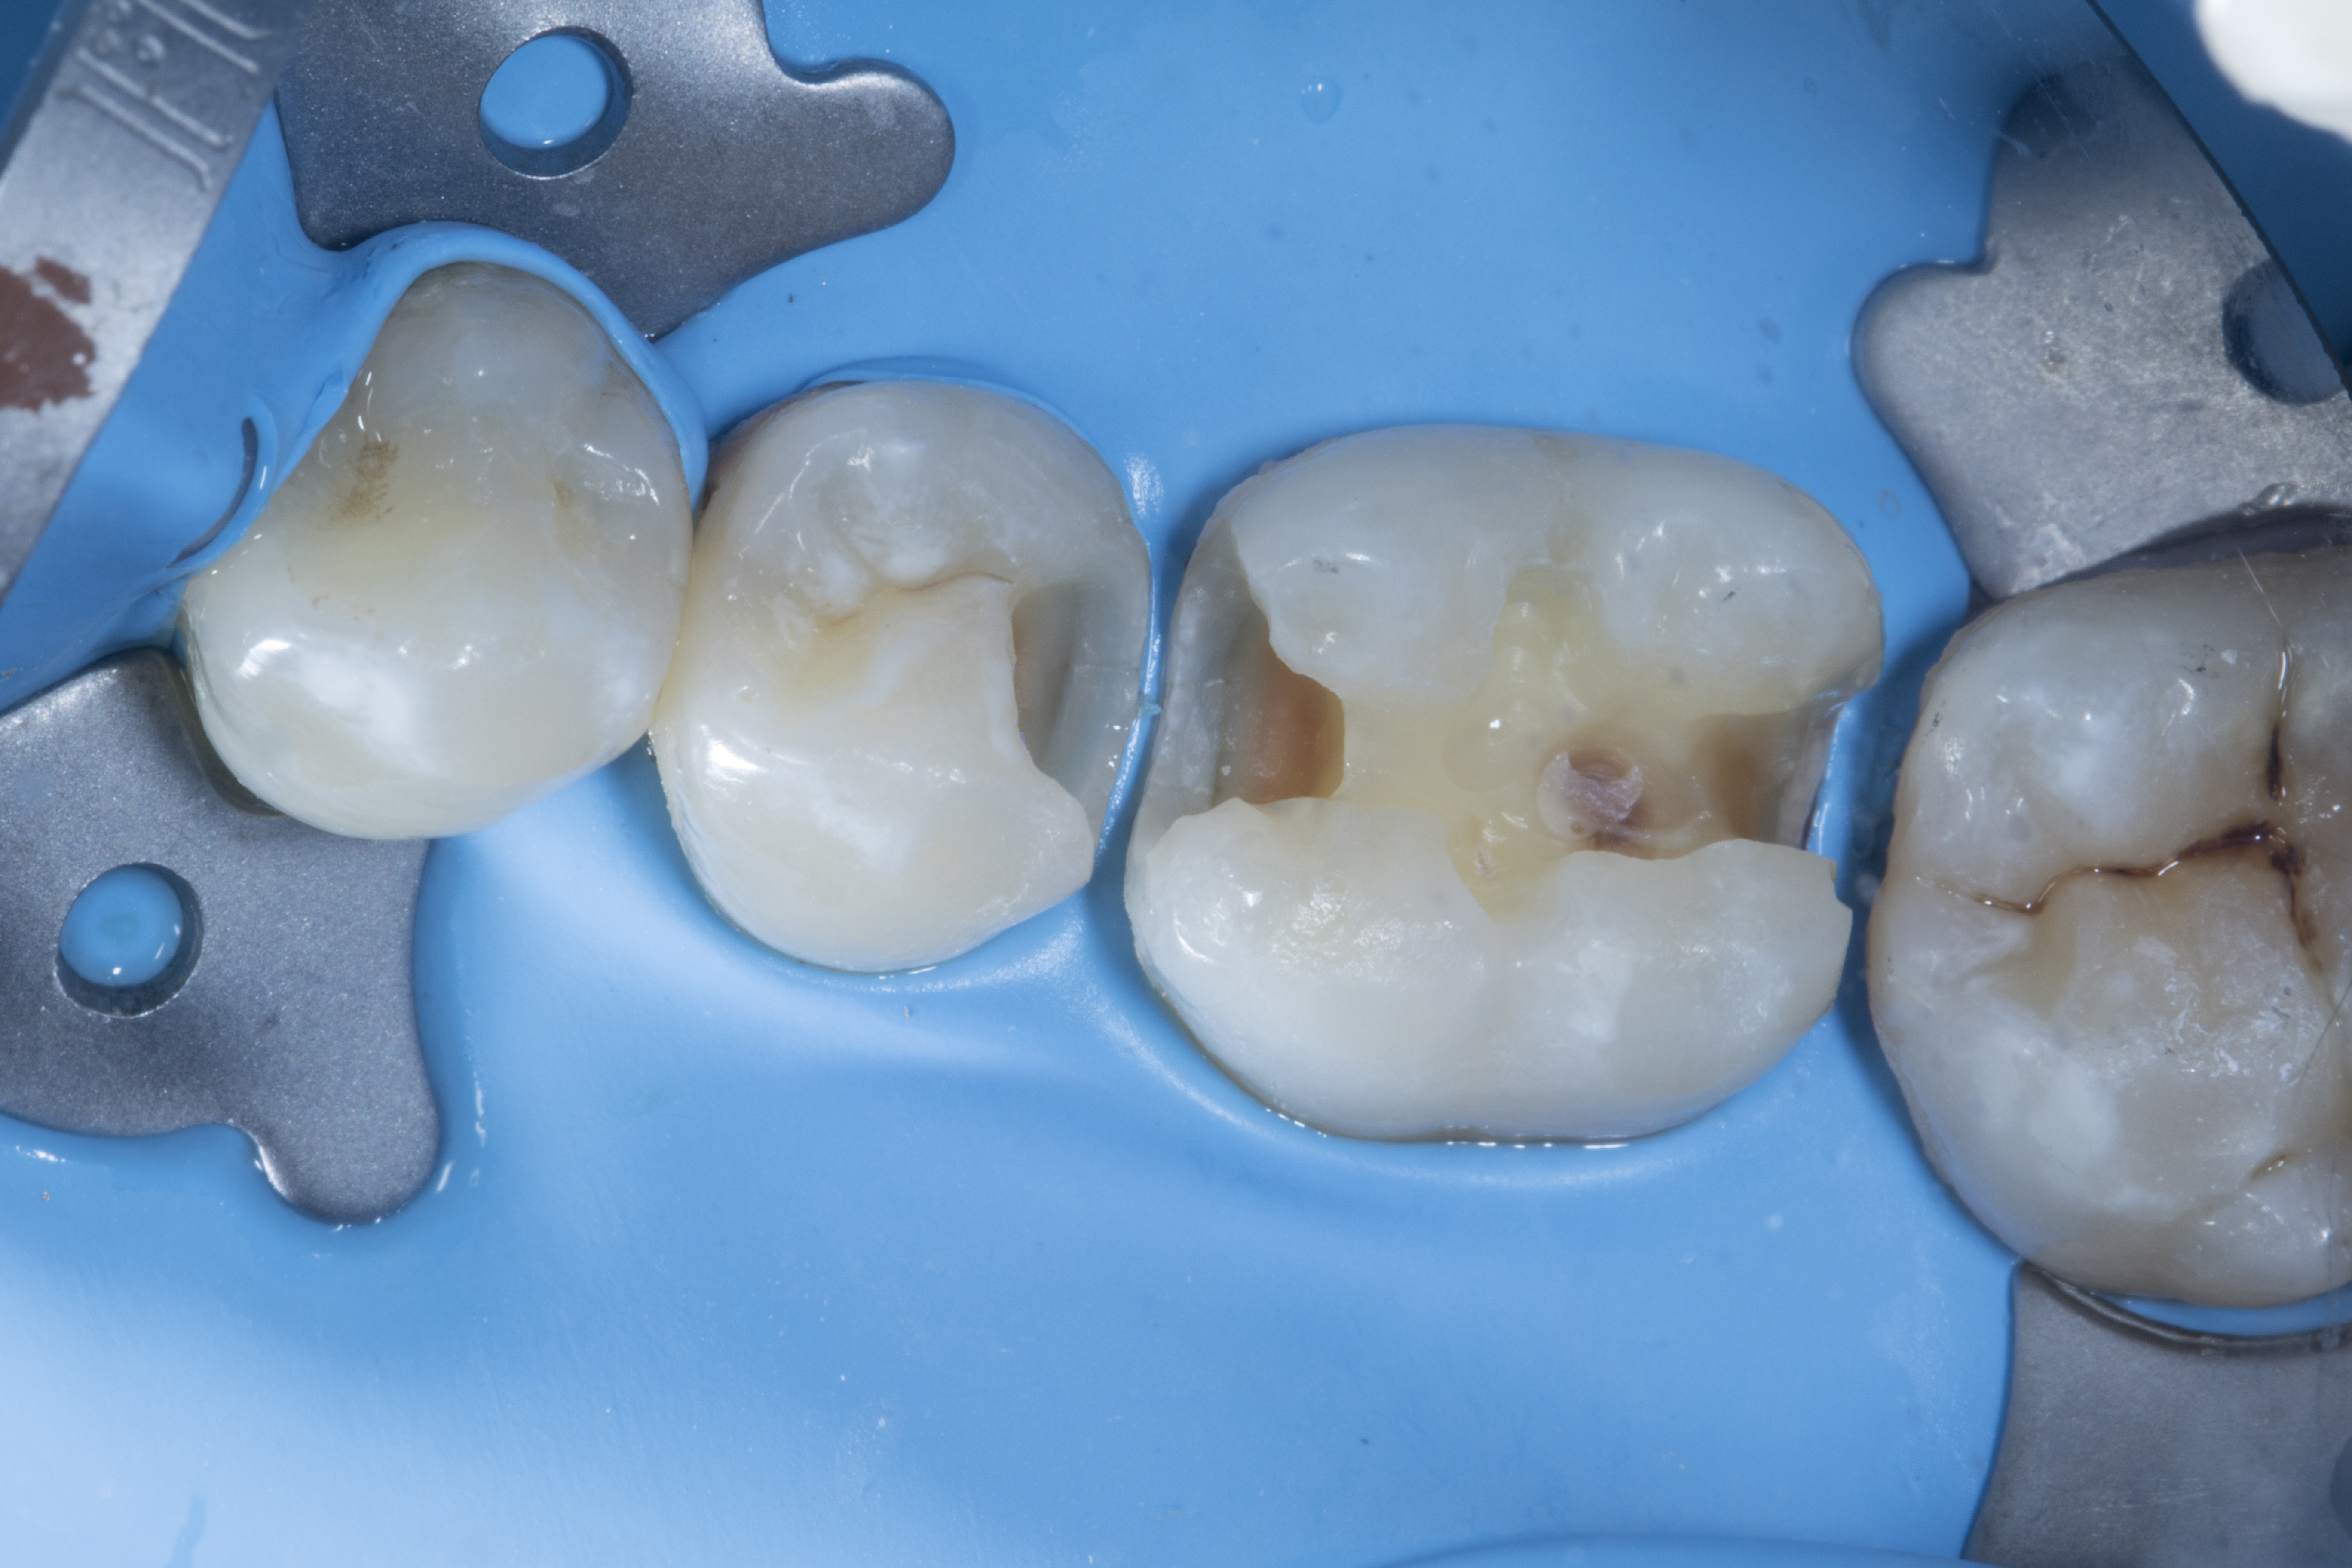

Figure 4

Figure 4. A Garrison pre-contour premolar FX100 (grey) band was placed in between #35 and #36 along with an extra small (yellow) Fusion Wedge.

Step 5 - After placing the band, a routine procedure of selective etching was completed with 32% phosphoric acid etchant.  Shofu 6th generation FL bond II primer and bond was then applied and photo cured as per instructions. A small amount of Shofu Beautiful Bulk Flow dentin shade was placed in the proximal box. (Do NOT photo cure) Due to its low viscosity, this material provides an excellent adaptation to irregular cavity geometry.  Next, a small amount of Beautifil LS II dentin shade A2 was placed in the proximal wall with a plastic composite instrument to create a perfect wall following the contour of the band and then photo cured.

Clinical tip: With this technique, the cavo surface margins can be sealed perfectly, with no air bubbles or under filled areas ensuring a tight seal in the proximal box.

Figure 5

Figure 5. Proximal wall was built with Beautifil LS II (Shofu) dentin shade A2, you can clearly see the natural contour.